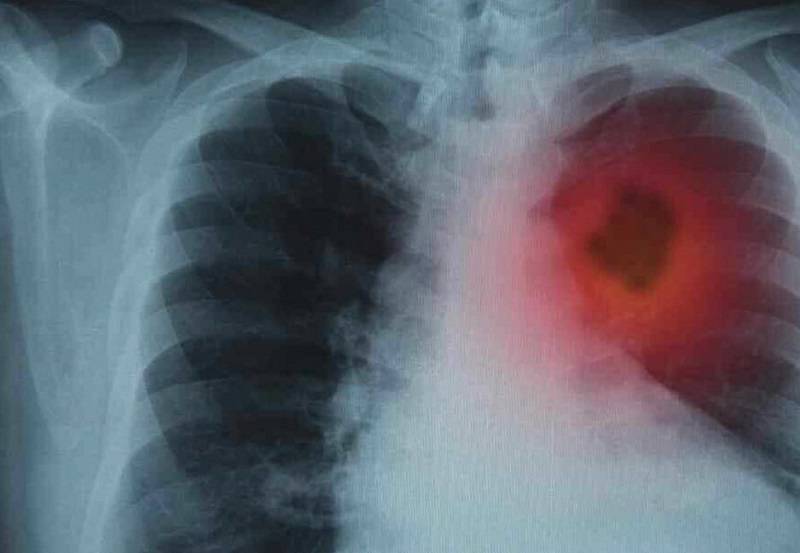

Yaklaşık 30 yıl sigara kullandıktan sonra sağlıklı hayat merkezine başvuran 49 yaşındaki Ali Duran, sigarayı bırakma sürecine ilişkin yaşadıklarını anlattı. Kalp rahatsızlığı nedeniyle doktorunun tavsiyesi üzerine sigarayı bırakmaya karar verdiğini belirten Duran, sigara bırakma polikliniğinde görev yapan hekimler ve uzman ekipler tarafından detaylı şekilde bilgilendirildiğini, gerekli ölçümlerin yapıldığını ve psikolojik destek aldığını ifade etti. Yaklaşık 3 aydır sigara kullanmadığını ifade eden Duran, nefes alışverişinin düzeldiğini, merdivenleri rahatlıkla çıkabildiğini ve enerjisinin arttığını belirterek, sigarayı bırakmak isteyen vatandaşları sağlıklı hayat merkezlerine davet etti.